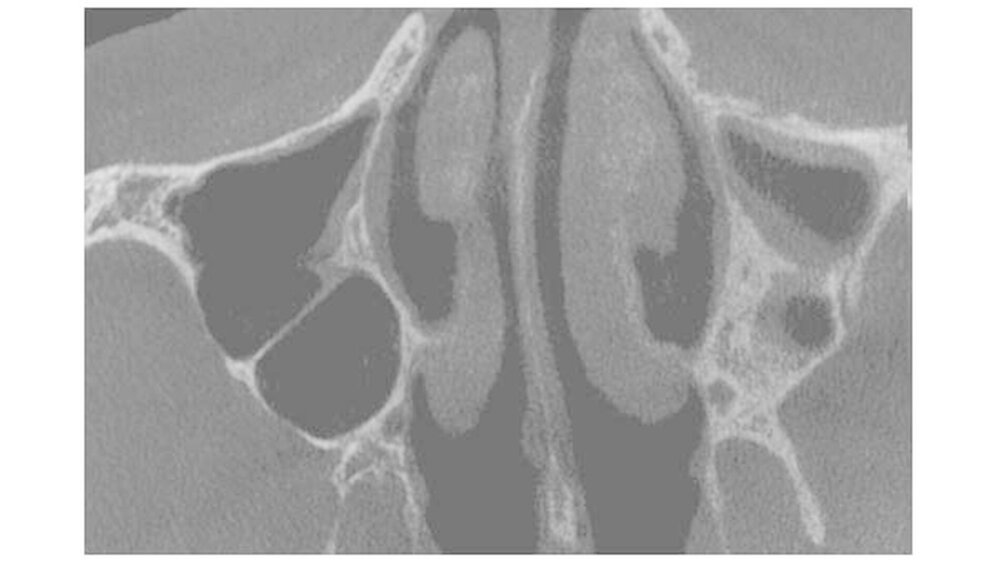

Im Frühjahr 2016 trat dann jedoch unter einer Brücke eine Knochennekrose im Oberkiefer links auf, die bei der Patientin Schmerzen und einen unangenehmen Geschmack im Mund verursachte. In Absprache mit der behandelnden Onkologin wurde der OP-Zeitpunkt festgelegt und nach einer Zytostatika-Pause erfolgte der MKG-chirurgische Eingriff in Narkose und unter kontinuierlicher Antibiotika-Therapie mit plastischer Deckung des Knochens.

Die Wundheilung verlief zunächst verzögert und etwas schleppend, aber letztendlich erfolgreich. Die Patientin behielt ihren Kiefer und wurde beschwerdefrei.